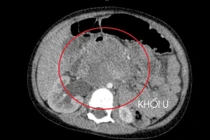

Kết hợp các phương tiện chẩn đoán hình ảnh hiện đại và xét nghiệm chuyên sâu, xác định trường hợp này là ung thư tinh hoàn lạc chỗ trong ổ bụng, kích thước rất lớn, đã có di căn hạch.

Qua khai thác tiền sử và thăm khám toàn diện, các bác sĩ nhận thấy bìu người bệnh không có tinh hoàn tương ứng, từ đó đặt ra nghi ngờ tinh hoàn lạc chỗ trong ổ bụng.